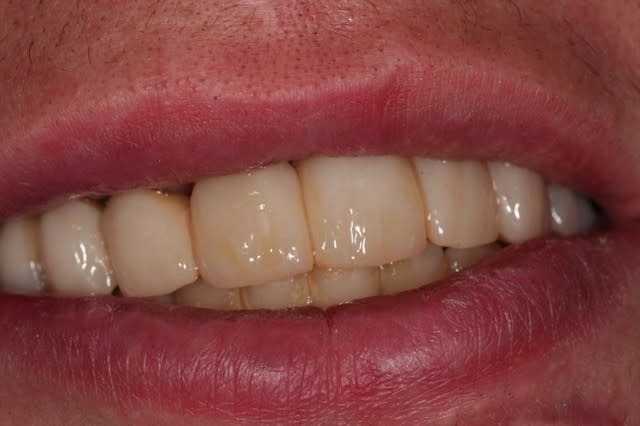

voilà, ça prend forme.

deuxième bridge provisoire.

j'ai sous-estimé le décalage de la 22, on y réfléchit.

je laisse mûrir complètement comme ça, et on verra à la fin si on fait de la mucco gingivale.

le patient est très content et s'en fout.

semaine prochaine: endos, compos et inlays....

Sourire plkk70 - Eugenol